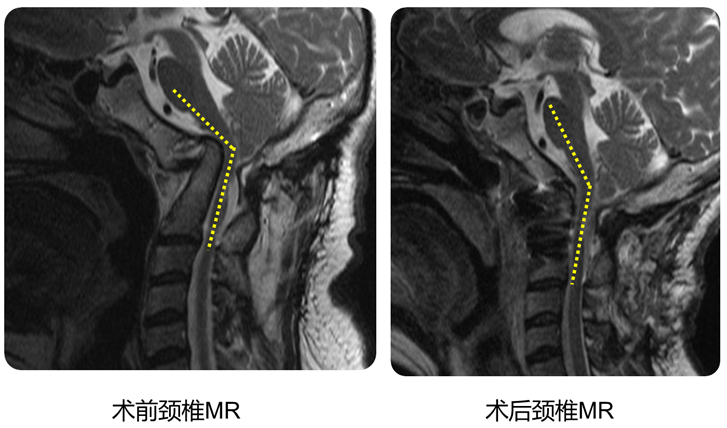

手术前后对比

可以看到:

陷入枕骨大孔的寰椎和齿突已经下拉复位,枕颈排列恢复正常

脑干压迫解除,延髓脊髓角恢复正常